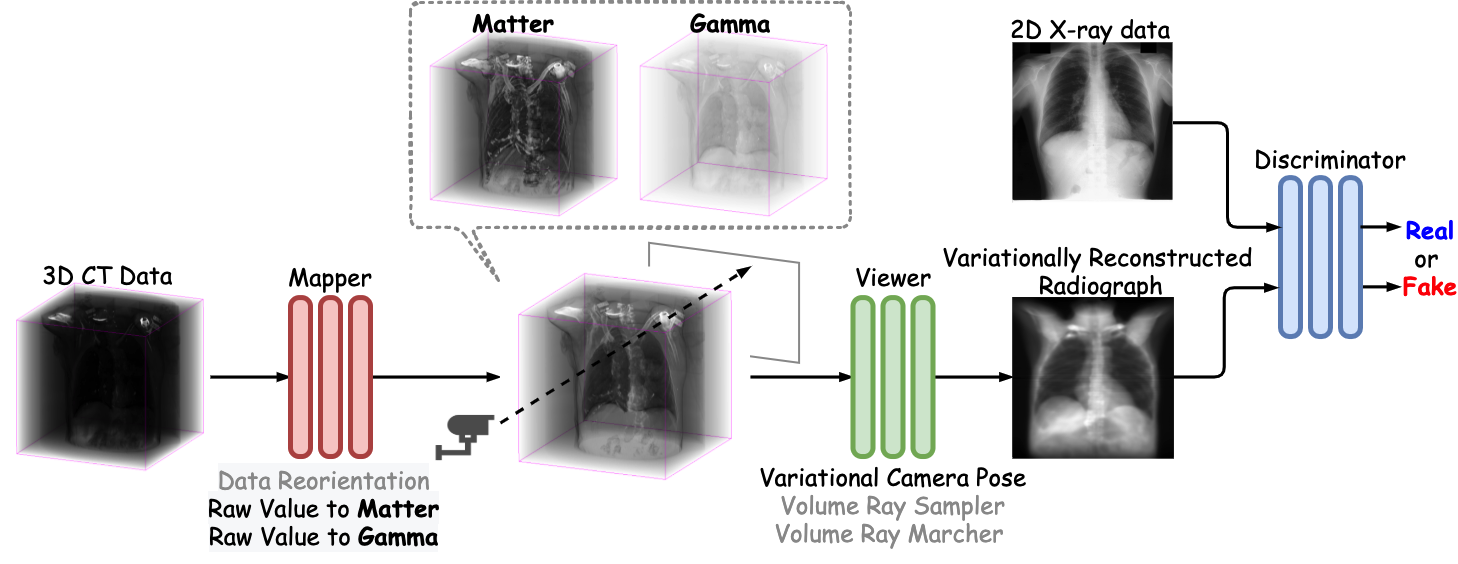

As shown in Fig. 2, the proposed method, NeRP, consists of these building blocks: a Generator includes a Mapper , a Viewer ; and a Discriminator that are parameterized by following objective functions:

The Mapper takes a single channel 3D CT volume , which has been normalized to produce a two-channel volume that consists of a Matter Field ( volume) combined with an Opacity Field ( volume). The subscripts indicate the shapes of tensors which have channel , depth , height , and width , respectively. They will be omitted for simplicity. The maximum bandwidth of is set 100-fold smaller than to foster the XR-like effect and discriminate different roles between them. Otherwise, these two channels are interchangeable and behave similarly to each other. Then the Viewer accepts the radiance , constructs the beam emission absorption model with ray bundle so that these rays can interact with the implicit volume function and the opacity . The proposed method also randomly samples a (variationally) perspective camera pose within a certain proximity of Field of View (FoV) to form the final image on the screen. The result is therefore called Variationally Reconstructed Radiographs (VRRs), as distinguish to DRRs. We employ Generative Adversarial Networks (GANs) [8] in XPGAN [7] to treat the VRR results as fake images and train the networks adversarially with the true XR samples that drawn from the real datasets . The adversarial loss is formally defined in Eq. 3 with the expectation of NeRP result is expanded in Eq. 4:

Last but not least, we add an per-pixel loss between the generated image and the ray tracing rendered version, weighted by to regularize the projected images to have the same anatomical structure as of its original CT volumes.